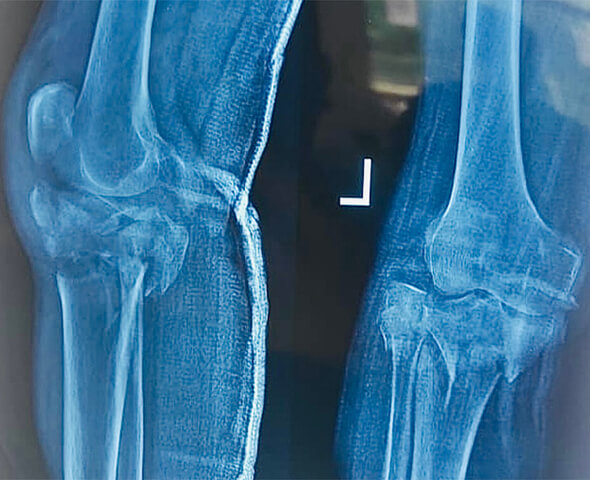

DEFORMITY CORRECTION